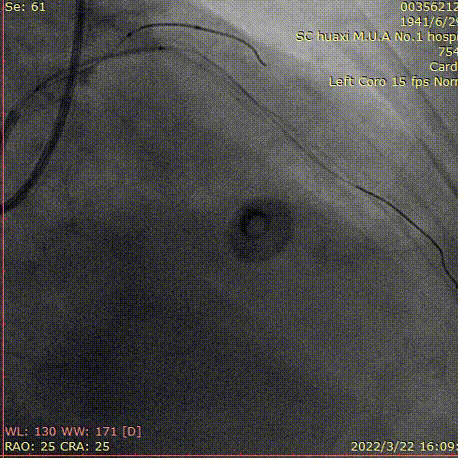

冠脉造影

造影说明:前降支开口重度狭窄,近段闭塞,入口不清,闭塞段长,走形不清。自身可见桥侧支形成,远端血管细小。